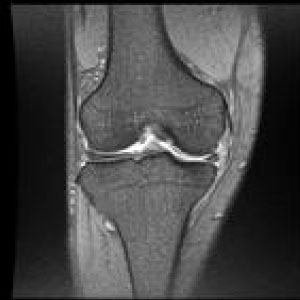

MRIはMagneticResonanceImageの略で強い磁石と電波によって人体の構造を見ることが出来る検査です。

頭部領域から脊椎・関節・骨疾患、腹部に至るまで全身部位の診断に役立ちます。

脳梗塞、脳腫瘍、脳動脈瘤、頚髄症、椎間板ヘルニア、脊柱管狭窄症、脊椎圧迫骨折、腱板損傷、各関節靭帯損傷、半月板損傷、骨壊死、肉離れ、骨腫瘍、軟部腫瘍、炎症、など